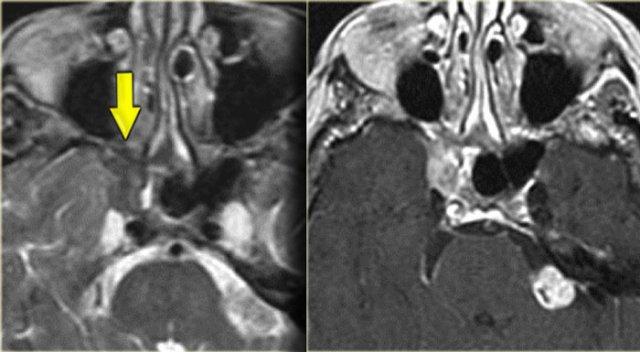

Nang nhầy (Mucocele)

Hình ảnh bên trái của một bệnh nhân bị viêm xoang cấp tính và bệnh lý tế bào khí sàng.

Bệnh nhân nhập viện với triệu chứng nhìn mờ.

Chú ý dịch trong mỏm yên trước trái.

Dây thần kinh thị giác chạy ở phía trong của nó.

Tiếp tục xem các hình ảnh mặt phẳng coronal.

Chuỗi xung T2W mặt phẳng coronal cho thấy sự giãn rộng của mỏm yên.

Chuỗi xung T1W cho thấy mất tín hiệu mỡ bình thường so với bên phải, và lan rộng vào đỉnh hốc mắt (mũi tên đỏ).

Đây là nang nhầy của mỏm yên trước với tổn thương thứ phát dây thần kinh thị giác.